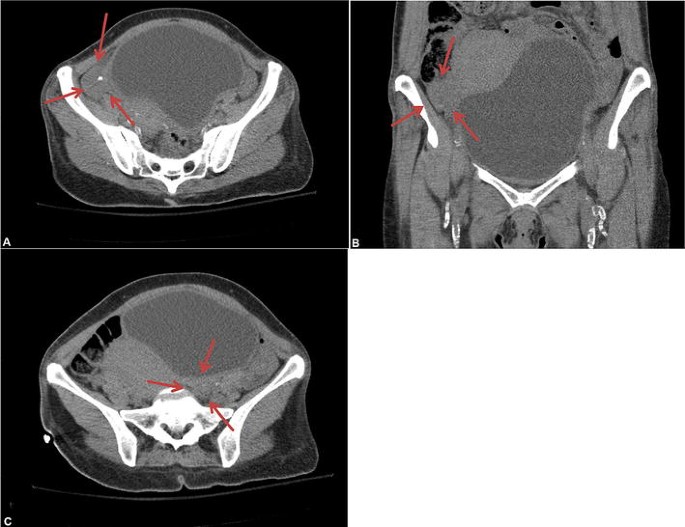

There are several potential causes of ovarian non-visualization. It could be caused by a medical condition such as polycystic ovary syndrome, which can cause the ovaries to be thickened or enlarged. Another potential cause is endometriosis, which can cause the ovaries to become inflamed. Ovarian cancer can also cause the ovaries to be difficult to visualize.

In some cases, the ovaries may not be visible due to the presence of scar tissue or adhesions. Adhesions are bands of scar tissue that can form in the abdomen or pelvis and can cause the ovaries to be difficult to visualize.

If the ovaries are not visualized, a doctor may order an ultrasound to get a better view of the ovaries. An ultrasound can help the doctor to identify any abnormalities in the ovaries, such as cysts or tumors. The ultrasound may also help to identify the cause of the non-visualization, such as endometriosis or adhesions.

If ovaries are not visualized during a pelvic ultrasound, it could be due to a number of different causes. It may be due to ovarian cysts or other masses in the ovaries that are blocking the view, or it could be due to the size and position of the ovary. It could also be due to a technical issue with the ultrasound machine.

In some cases, the ovaries may be too small to be seen, or they may be hidden behind other structures in the pelvis, such as the uterus or bowel. If this is the case, a different type of scan, such as an MRI or CT scan, may be required to view the ovaries.